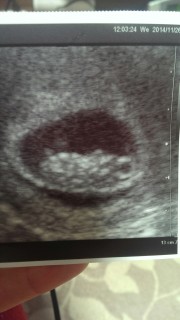

初診から2週間後の9週目。 大きさ22.4㎜。 ただの丸い形から一気に人間らしくなっててびっくり!元気に動いてたので、写真がブレブレ。その中からのベストショット。かわいいな。

8週目につわりがない日があったりして、不安になったりしたんですが9週目に育ってる姿を見て安心しました。 これは頭を下にして、横から見てるそうです。 二頭身で手も足もどこもかしこも可愛くて泣きそうになりました。へその緒もきれいに見えてちょっと感動しました。 どうかこのまま元気に育ってくれますように。。。

大きさ的に 週数変更で10週が9週に変更になりました。前回前々回と機械が違うようで 映りは少し見にくいかな。CRL2.04 、 2週間で倍になりました。 診察が押していた為、診察時間が短く残念だけど次回はもう少し見てたいなー

初めて心音を聞きました。すごい速さで力強く動いててびっくり★CRLは22ミリでした。 出血があったりしたので不安でしたが、安心しました^^ 元気に育ってね!